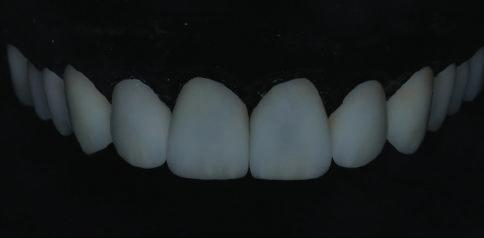

Пациентът постъпи в клиниката с молба за тотална рехабилитация на усмивката. Той не харесваше централ ните си резци, които според него бяха твърде къси и квадратни. Имаше раз стояние от медиално и дистално на латералните му резци. Друго сериоз но оплакване бе свързано с металоке рамичната корона на зъб 12, която бе жълтеникава и неестетична, като цяло не харесваше вида на венците си и както самият той се изразяваше, „вижда се прекалено много от венците при усмивка“.

След диагностиката бяха направени екстра- и интраорални снимки, както и рентгенографии; професионалното почистване бе от изключителна важ ност, бяха дадени и инструкции за лич на орална хигиена. Бе направено интра орално сканиране с Medit i500. Цялата тази информация бе използ вана в приложението Smilecloud за 2D биометричен дизайн. В приложението са налични естест вени форми на зъбите и щом бяха под брани зъби и бе направен дизайн

библиотеката на Exocad. Струва си да се отбележи, че 2D дизайнът от Smile Cloud бе спазен до последния детайл в Exocad smile creator с цел да се създаде 3D obj файл със зъбните форми. След като естетичният дизайн бе готов в model creator модула на Exocad, адитивен 3D мок-ъп модел бе експорти ран и принтиран от принтер Formlabs 3. Моделът бе използван за направата на силиконов водач, за да се изготви мо тивационен мок-ъп в устата на паци ента и да се оценят естетичните па раметри. След като пациентът одобри вида на усмивката си, мок-ъпът бе използван за финализиране дизайна на усмивка та. Мок-ъпът бе използван също така като водач по време на мекотъканна та хирургия, както и при препарация на зъбите.

Препарираните зъби бяха импорти рани в Exocad и насложени върху ес тествените форми от биометричния дизайн, като така стана ясно дали зъ бите са били препарирани коректно. По този начин зъболекарят и зъботехни кът работят в една и съща екосистема и резултатът е оптимален. С короната се справихме чрез диги тална редукция на циркония в Exocad, като по този начин на практика създа дохме циркониево кепе, след което про изведохме фасета от IPS Empress Cad Multi. Кепето от Katana Zirconia на зъб 12 с букално послойно нанесена керами ка бе фрезовано (послойното нанасяне бе направено, за да се подобри връзката и да се осигури адхезивно циментиране на фасетата към циркониевото кепе, както и за да се напасне цветът към този на съседните зъби). При първото сканиране регистрирах ме цялата горна зъбна дъга, така че, ко гато се наложи да сканираме повторно, бе изтрит и сканиран наново само зъб 12, тъй като венците не бяха отдръп нати при второто сканиране.

Една седмица след препарацията на зъбите и циментирането на цирко ниевото кепе бяха изработени 12 IPS Empress Cad Multi фасети. Макро- и микротекстурата на фасе тите бяха направени на ръка, след кое то бяха нанесени 3D характеризации с боички, а полирането отново бе напра вено ръчно, за да им се придаде естест вен и естетичен вид. Предизвикателството тук беше короната да има същите оптични характеристики като тези на остана лите зъби при естествена светлина, през поляризационен и флуоресцентен филтър. 3D принтерът бе Fromlabs, софтуерът за фрезоване – Mill Box, а фрез апаратът –imes icore CORiTEC 350i. В крайна сметка постигнахме ес тествен вид на усмивката с натурал на зъбна морфология при изцяло диги тален протокол, при който дизайнът бе направен първоначално и през всич ки етапи на лечението се придържахме към него до самия край Излишно е да отбелязваме, че всички сме удовлетворени от постигнатото! Преди След Победител в категория „Клиничен случай с изцяло дигитален протокол“ в конкурса „Усмивка на годината 2022“

11Dental Tribune Bulgarian Edition / октомври 2022 г. Преди лечението Фиг. 1 Фиг. 2 Фиг. 3 Фиг. 4 Фиг. 5 Фиг. 6 Фиг. 7 Фиг. 9 Фиг. 10 Фиг. 11 Фиг. 8 Фиг. 12 Фиг. 13